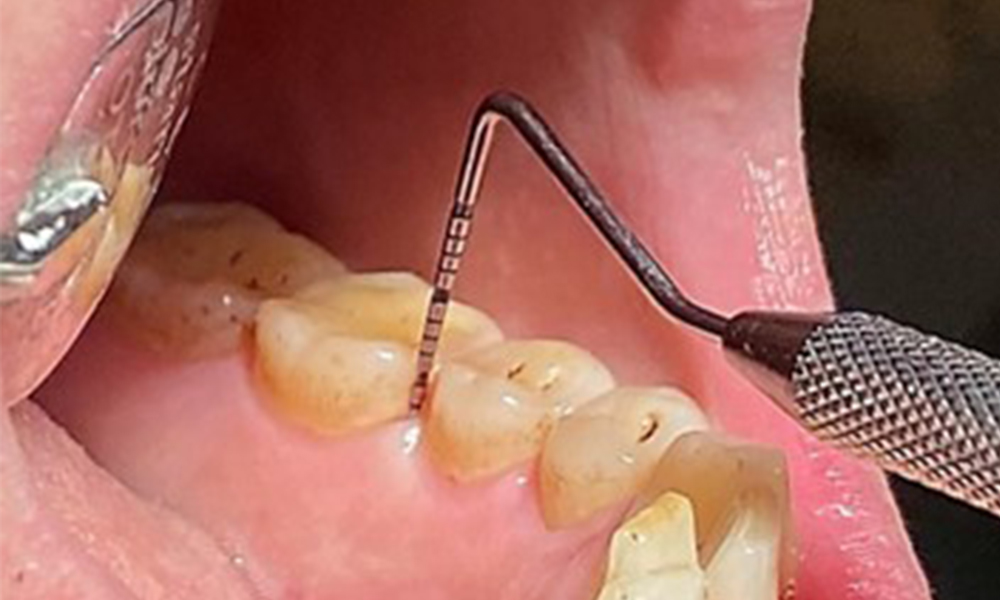

Due to the otherwise favourable general medical condition, the needs determined during the intraoral examination will be decisive for their treatment. It will be essential to periodically determine the probing depths. Gingival bleeding decreases in smokers, which is why the clinical diagnosis of periodontitis can only be made by probing (Fig. 7). Placing exclusive focus on the determination of bleeding indices may obscure existing periodontitis or gingivitis. (5)

Pocket probing (BOP) with depiction of tooth 36 lingual

Fig. 7 Pocket probing (BOP) with depiction of tooth 36 lingual, © Dr R. Krapf

3. It is important to document findings during the therapeutic appointment. Bleeding-on-probing (BOP) status to measure periodontal pocket depth in the early stages of disease must be determined during each appointment. This is particularly important in smokers due to decreased tissue perfusion.